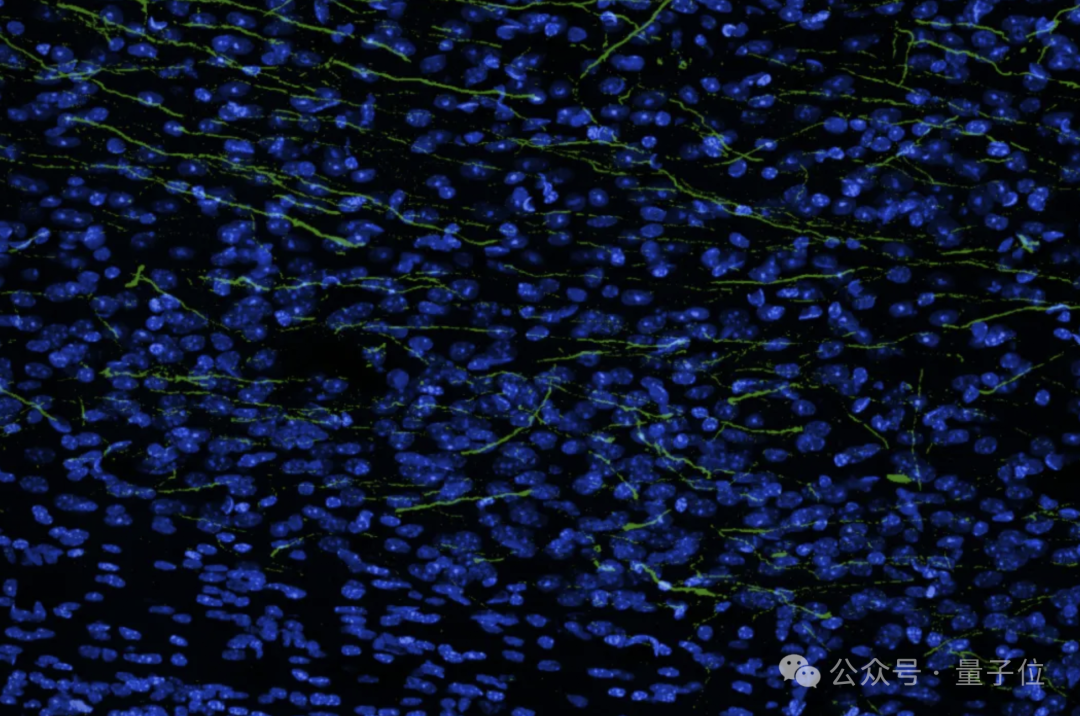

如图所示,绿色突出显示的细胞是实际的神经元轴突和树突,它们从生物混合移植物中延伸出来,在整个大脑中形成能够传输信息的连接。

结果发现约52%的微孔中含有表达荧光蛋白的神经元,这些神经元向皮层内投射复杂突起,表现出自发的钙活动,组织学证实移植神经元与宿主脑紧密耦合。